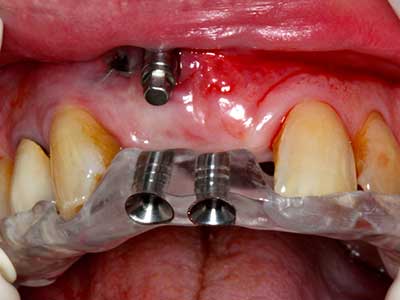

Piezosurgery has additional advantages when harvesting bone blocks. In addition to the high precision with osteotomy described above, the use of the thin saw tips specifically minimizes loss of material. Greater loss of material during harvesting can be expected with the thicker instrument tips, particularly when using Lindemann drills (Lakshmiganthan, Gokulanathan et al. 2012). The basal separation, which is necessary particularly for retromolar block transplants, is simplified by specially designed rectangular saws, with the result that piezosurgery is viewed as a precise, simple and safe procedure for harvesting retromolar bone blocks (Happe 2007) (Fig. 1-12).

Indication: Bone splitting

Bone tissue is not simply a mineral structure but also contains a substantial proportion of collagen fibres. This means it not only has good compressive strength but also a degree of flexibility, which can be taken advantage of when performing bone augmentations. In the classical expansion procedure using bone splitting, the atrophied alveolar ridge is split longitudinally and carefully expanded after reaching an adequate osteotomy depth (Fig. 13-16), ideally without substantial removal of the periosteum (Brugnami, Caiazzo et al. 2014, Stricker, Fleiner et al. 2014). Screw and plate systems with increasing expansion distance have proven effective in separating the two bone lamellae while remaining below the fracture threshold. In general, residual bone widths of at least 3–4 mm are required (Chiapasco, Zaniboni et al. 2006) to guarantee adequate flexibility and sufficient bone coverage of the future implants. If necessary, a vertical relief osteotomy on one or both sides can improve flexibility. A combination with additional augmentation techniques, particularly on the buccal side, has been described as an alternative to the classical technique.

The splitting procedure is particularly atraumatic and there is no significant loss of dimension when using piezosaws, and there are no significant differences between implants in split jaws and implants in an alveolar ridge without a bone deficit (Chiapasco, Zaniboni et al. 2006, Danza, Guidi et al. 2009). However, sufficient continuous irrigation is essential, particularly with locally restricted and deep splitting to prevent thermal stress in the apical osteotomy regions.